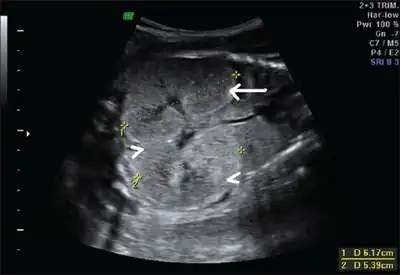

Ultrasonography is the primary method to evaluate autosomal recessive polycystic kidney disease, particularly in the perinatal and neonatal stages.[3]

Fetus with bilateral enlarged/hyperechogenic kidneys arrow & diminished cortico-medullary differentiation arrowhead